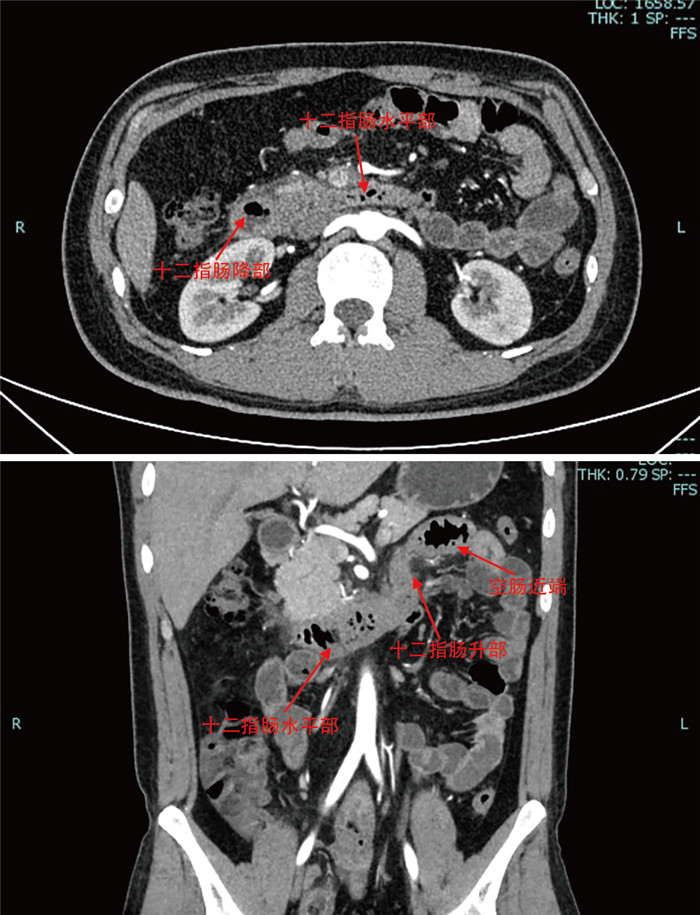

摘要:

通过回顾成人腹型过敏性紫癜误诊病例,分析原因并结合临床文献资料,总结腹型过敏性紫癜疾病特点,降低误诊率。本文回顾分析了2022年7月收治的1例被误诊为急性胃肠炎的成人腹型过敏性紫癜患者的临床资料,该例患者在腹痛后期出现皮肤紫癜,同时寻求多学科会诊,更改诊断为腹型过敏性紫癜,予以糖皮质激素、抗过敏药物等对症治疗后病情好转出院。腹型过敏性紫癜少见,而成人发病率更低,因缺乏特征性临床表现及特异性辅助检查,误诊率高,临床工作者应吸取经验教训,避免误诊错治。